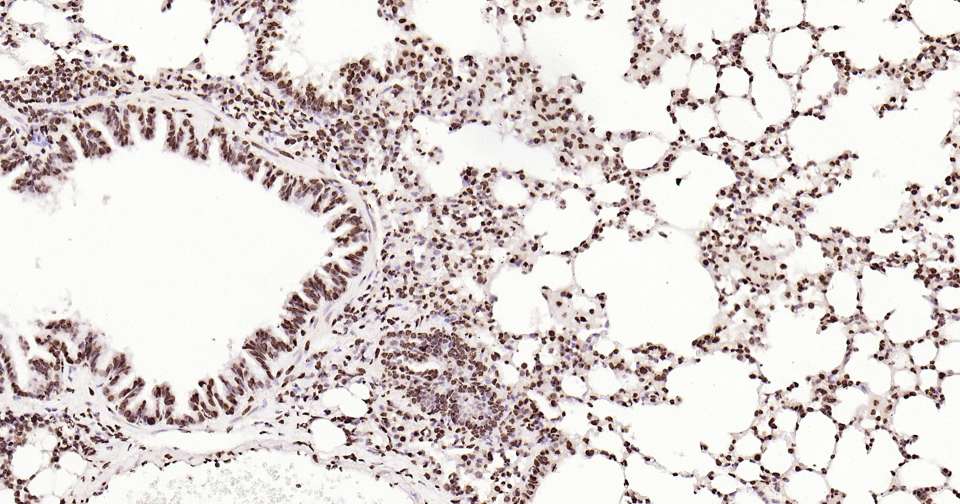

Immunohistochemical analysis of paraffin embedded mouse colon tissue slide using IHC0308M (Mouse Histone H2A.X Kit).

Immunohistochemical analysis of paraffin embedded mouse testis tissue slide using IHC0308M (Mouse Histone H2A.X Kit).

Immunohistochemical analysis of paraffin embedded mouse lung tissue slide using IHC0308M (Mouse Histone H2A.X Kit).